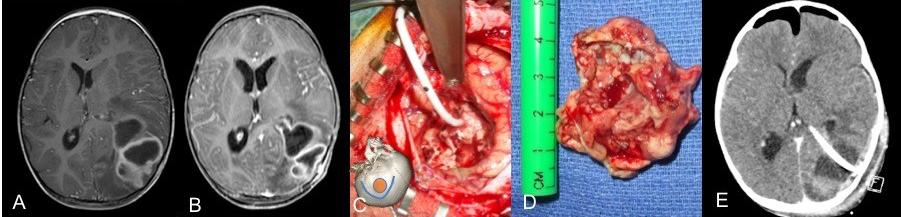

la chirurgie

elle consiste au minimum en une ponction de l’abcès, par trépanation, éventuellement guidée par neuronavigation, ou par ponction trans-fontanellaire éventuellement sous contrôle échographique. il s’agit le plus souvent d’une urgence chirurgicale en raison du risque d’aggravation rapide au plan neurologique comme au plan infectieux.

en pédiatrie, on note cependant que plus de la moitié des patients nécessitent une craniotomie, en raison :

- d’un diagnostic erroné (tumeur)

au total, de nombreux patients nécessitent plus d’une intervention (ci-contre).

elle est prescrite de façon probabiliste (en fonction du ou des germes attendus, puis adaptée aux germes isolés, par voie intra-veineuse et prolongée plusieurs semaines, sa durée sera déterminée en fonction de l’évolution en imagerie. on note qu’après craniotomie et excision de l’abcès, l’imagerie est normalisée très rapidement.